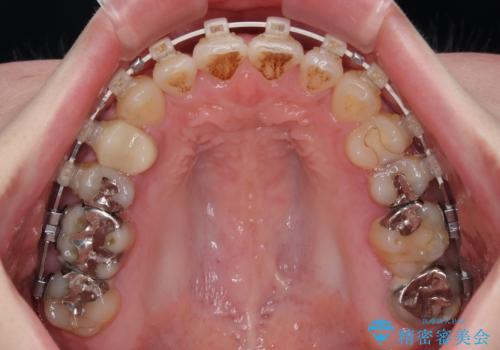

開咬をワイヤー装置で矯正治療

- 審美装置

- 10ヶ月

治療開始から8ヶ月ほどで遠方への転勤が決まりましたが、歯列は概ね整っていたため、その後は東京出張を狙って治療を終える処置を行うことができました。